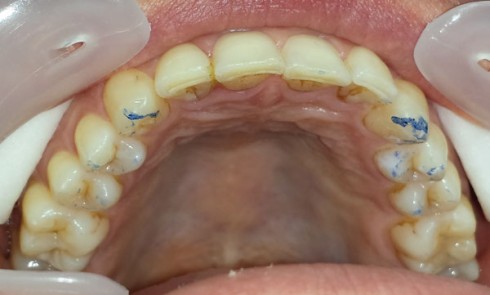

Article réservé à nos abonnés Choix d’une approche additive dans les traitements d’usures érosives et attritives : intérêts des full mock up

Les patients atteints d’érosion/usure de nature chimique consultent de manière quasi exponentielle au sein des cabinets, avec des degrés d’atteinte...